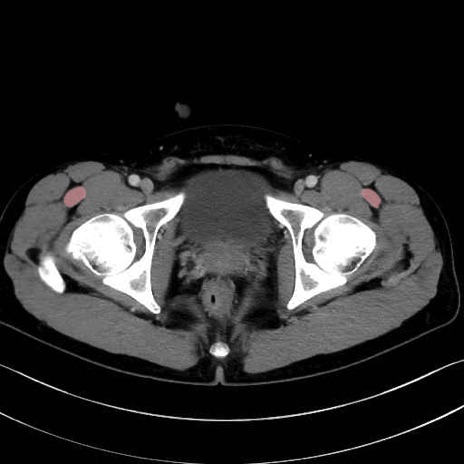

大腿筋膜張筋 (Tensor fasciae latae)

4. 深層外旋六筋(股関節の深部)

梨状筋 (Piriformis)

内閉鎖筋 (Obturator internus)